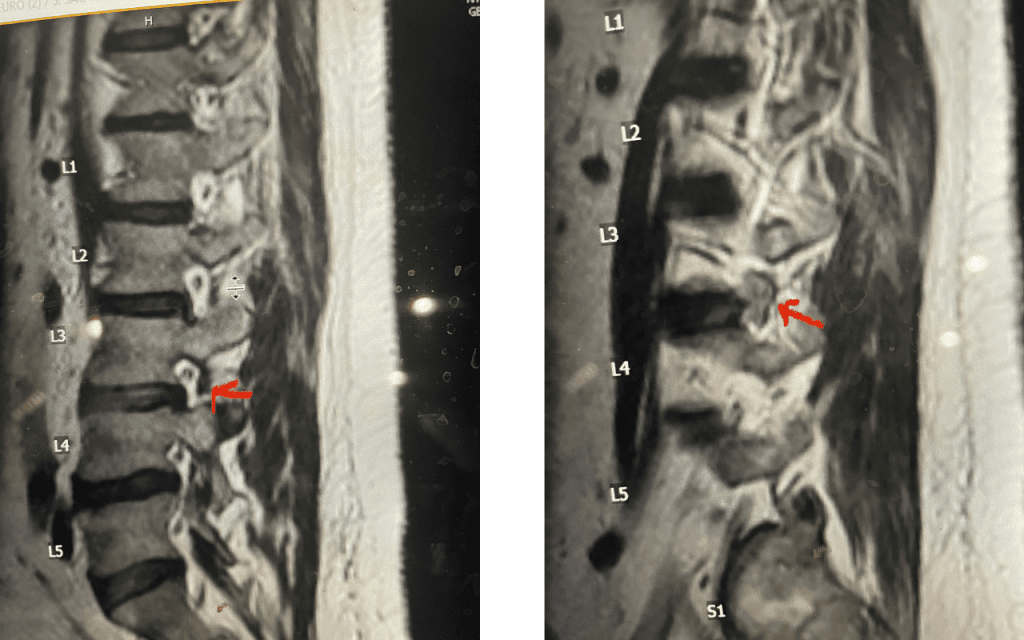

Fig 7: Sagittal T2-weighted lumbar MRI with side by side comparison of the normal open right L3-4 foramen (red arrow) compared to the left L3-4 foramen filled with a large disc fragment (red arrow).

Here is a case of an extraforaminal disc fragment causing severe pain and weakness: This 60-year-old male presented with severe anterior thigh pain, numbness, and weakness for 3 weeks. He had failed epidural steroid injections. His left leg buckled when he walked. Imaging revealed a massive left L3-4 extraforaminal disc herniation, beyond the facet (Fig 6). This was severely compressing the left L3 nerve root in the L3-4 foramen (Fig 7). It was felt that the patient required surgery, as he would not be able to participate in physical therapy and had a neurological deficit. We performed an extraforaminal approach and removed a massive disc fragment that was revealed as the intertransverse membrane was reflected from the L4 transverse process-facet junction. We were able to visualize the L3 spinal root exiting above that had been compressed by the large fragment we removed (Fig 8). The patient post-op had a dramatic improvement neurologically and with significantly improved pain in his leg.